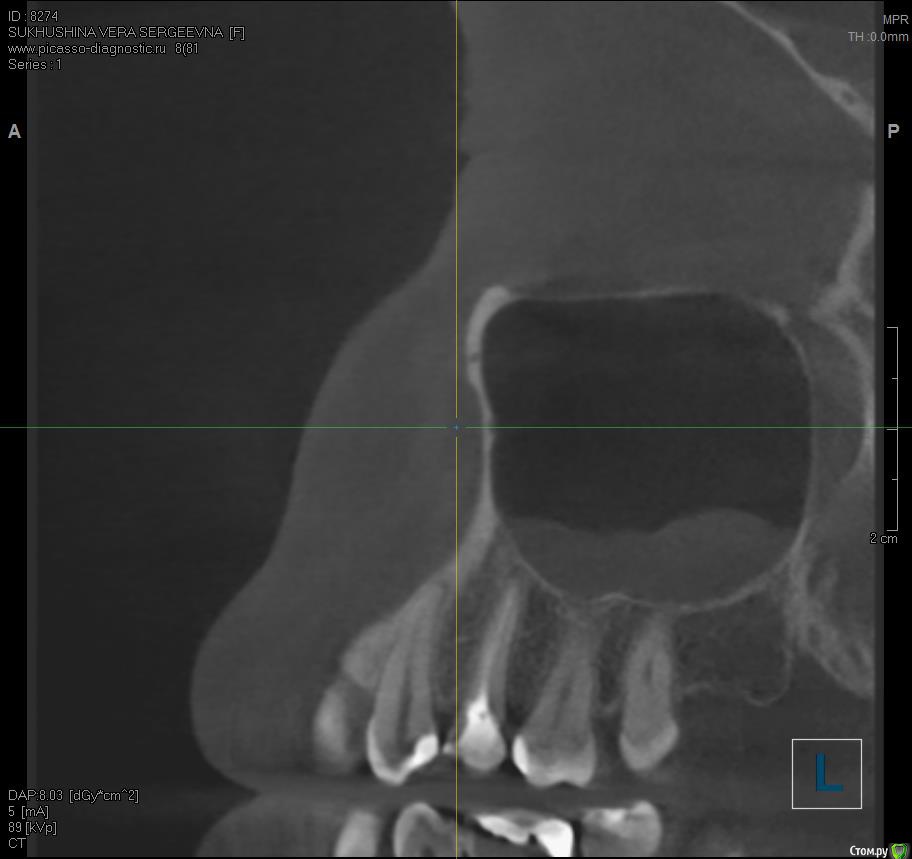

Verasss Опубликовано 23 ноября, 2016 Автор Поделиться Опубликовано 23 ноября, 2016 Сделала ещё 1 кт, спустя почти 2,5 месяца после первого. Посмотрите, пожалуйста, есть ли изменения? Напомню, что пункцию гайморовой мне сделали. Ссылка на комментарий

Verasss Опубликовано 28 сентября, 2016 Автор Поделиться Опубликовано 28 сентября, 2016 эх, ну два врача мне зуб делали. один нерв вынимал, второй пломбировал, так уж вышло. и снимки там разных проекций и КТ есть. Дело не в этом. Когда оставила зуб в покое, жизнь постепенно наладилась, но вернулась с дождями-холодами числа 22.09.Уже и бегала к хирургу, показаний для разреза нет, отека нет. По КТ вроде в гайморовой то ли киста то ли полипы. Гноя, насморка нет. Болит и она периодически.Но больше беспокоит, что ноет десна и ощущение мягкости, ноет не в карманах, а в где-то в верхушке корня что ли. Если сильно втянуть воздух, то как бы весь зуб ощущается в этом периодонте и отдает в гайморову. И 6-ка тоже стала немного чувствительной перкусии.На холод-тепло сам зуб не реагирует, сам зуб вообще не беспокоит, только ткани вокруг него.А как болит канал мне показали, дунув хорошенько воздухом в стоматологии на 6-ку рядом (там пломба близко к нерву), и вот это не такая боль. А вообще, день на день не приходится. То гайморова беспокоит, до десна, то всё вместе, то почти ничего. Основные раздражители: механические (например, тряска в маршрутке, трогание зуба языком, чистка зубной нитью, твердая пища), дожди-холода, психологические (тревога, стресс). Причем в один день зуб может не беспокоить, ткани ощущаться твердыми, а в другой разныться. КТ прилагаю архивом от 08.09. К сожалению, чтобы нарезать фотки, мне нужно переустанавливать память с бОльшей мощностью, а такой возможности у меня пока нет. Надеюсь, кто-нибудь посмотрит). https://yadi.sk/d/5Zw3pMFevs7Hd Делать снимки свежие уже боюсь, уже много чего наделано, и на визиографе, и простых рентгенов, и КТ. В общей сложности где-то +10. Ещё и лоры требуют, чтоб я делала КТ пазух с их точки зрения, а государственный - чтоб вообще рентген сделала в поликлинике. В общем, засада. Хочется какой-то универсальный сделать. Может, физио поделать? Т.е. у меня как пациента по-прежнему 2 варианта: или острое воспаление, которое не видит КТ от недопломбировки верхушки или занесения чего-либо, а гноя нет, может, иммунитет хилый, свищ не делает, а если вскрыть зуб, то пойдет? был отек губы и немного щеки как-то после очередных постукиваний у стоматолога, но я выпила антибиотик, и на следующий день прошло. (плюс я антибиотики пропила курсом и анальгин иногда); и вообще воспаления у меня всегда так проходят сразу в хронической форме, долго и мутно, без горячки и адовых болей. (Хотя....если можно как-то сравнить с ногой, например, в прошлом году, то там был гнойник с опуханием всей стопы, всё как в учебнике...) Или это сильная травма зуба и периодонта при пломбировке горячей гутапперчей, усиленная моими походами к стоматологам и постукиванием там по оному. Гайморова присоединилась не сразу, а где-то недели через 2 после пломбировки. Т.е. как-то мне видится, что врачи правы,и там не гайморит, а была уже большая киста или полипы, которую эта агрессивная пломбировка потревожила. Спасибо!Если кто ответит, и на том спасибо). Ссылка на комментарий

DmitrySH Опубликовано 8 октября, 2016 Поделиться Опубликовано 8 октября, 2016 В таком виде КТ малоинформативно. Но гайморита нет. Ссылка на комментарий